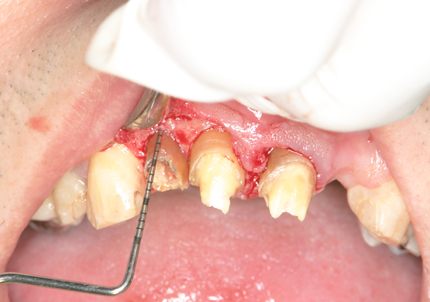

3.歯冠長延長術(2014年11月)

➡ 歯冠長延長術とは・・・歯ぐきや骨の位置を調整して、歯の見えている部分(歯冠)を意図的に長くする治療。歯ぐきがかぶって歯が短く見える審美的な問題、歯周病治療や補綴治療を成功させるための前処置等として行われる。

【 縫合 】

【 歯周パック 】